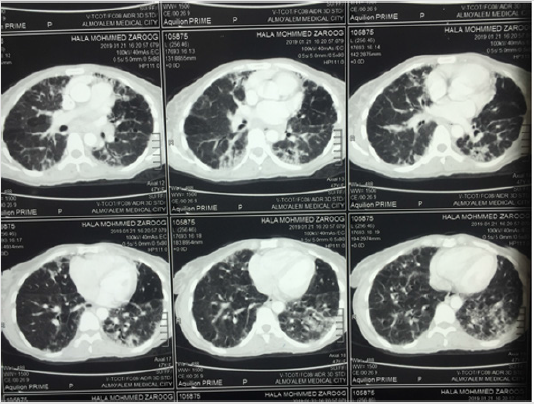

We are reporting a case of 48 years old female primary school teacher, with 5 children, married for 20 years, residents at Algaily at Khartoum north state, Sudan. Her medical history in the past is clear, had no smoking history, she was healthy and well until 3 years ago, she started to endure from a cough, which was lasting through all the day, productive with whitish small amount odourless sputum, not associated with fever or sweating, stationary in its course lasting for more than 4 months then she sought medical attention, as Sudan is a pandemic area for tuberculosis, initial workup for TB clinically and laboratory was done but clear and the investigation reveals no evidence of infection. Then she retained back again seeking for medical care at chest physician, the auscultation reveals Coarse crackles disappear after coughing on both sides of the chest at middle and lower zones, in addition to localized chest pain not radiated and associated with vomiting. He asked for furthermore workup, based on clinical features along with chest CT scan which showed there were bilateral septal thickening, ground-glass opacity mild bronchiectasis changes. he put his diagnosis as Bronchiectasis (Figure 1).

Figure 1: CT chest of the patient, shows bilateral septal thickening, ground-glass opacity mild bronchiectasis changes.

Rheumatoid arthritis has a strong association with a lot of pulmonary conditions, such as Tuberculosis, pleural effusions, bronchiolitis and BR [6]. The association of RA and BR has been recognized earlier, with the first published report in 1960 [7]. Bronchiectasis is a long-term condition that is characterized by permanent bronchial dilation [8]. The presented patient endure the clinical features of the disease such as sputum production, cough and repeated infections, In addition, CT chest done to the patient showed bilateral septal thickening and ground-glass opacity mild bronchiectasis changes (Figure 1), high resolution CT scan of the chest is considered as the gold standard for confirmation of bronchiectasis [9]. forced vital capacity [FVC], lung function test, sputum bacteriological culture and chest radiograph can also be needed to establish a proper diagnosis [10].Others differential respiratory illnesses such as TB has been laboratory excluded.